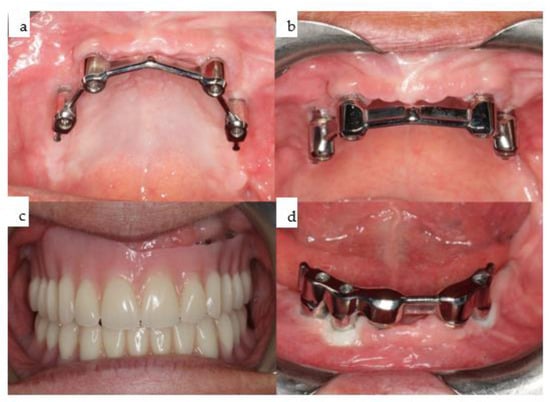

Twenty-one months post microvascular bone flap and previous soft tissue reconstruction, a subperiosteal implant containing four posts was rigidly fixated with 20 2.0 self-tapping screws, including bilateral long extensions as booms to each ascending ramus (Figure 20). The design aimed to maximize fixation at the bilateral ascending mandibular ramus area, benefiting from the well-vascularized thick soft tissue envelope provided by the pterygoid–masseteric–muscular sling. A meander-shaped design for the IPS Implants® Preprosthetic was chosen to allow for secure placement on top of the fibular bone graft to allow for a secure one-fit-only shape of the footplate framework and reduce the amount of metal around the pillars passing through the overlying soft tissues (Figure 20 and Figure 21). The patient-specific subperiosteal implant was placed during outpatient surgery under general anesthesia. The first provisional superstructure for the mandibular subperiosteal implant was a high-water-designed non-precious metallic bar-based screw-retained prosthesis on four implant posts (Figure 21 and Figure 22), recommended to prevent compression to the underlying soft tissues. Six conventional bone-level tapered dental implants were placed in the maxilla guided by CAD/CAM drill guides designed with coDiagnostiX® software (Straumann, Basel, Switzerland) and printed with a Formlab 3D printer (Figure 18 and Figure 22).

Figure 22. (ad): The same IPS Implants® Preprosthetic during intraoral placement (a), following the final prosthodontic restoration including the screw-retained non-precious metallic bar onto the IPS Implants® Preprosthetic in the mandible (b), along with the removable overdenture on top (c), and in function with the upper overdenture, which was also bar-retained (d).